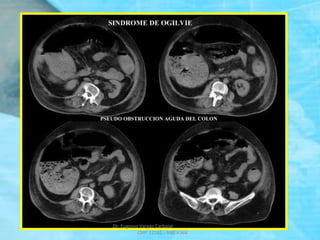

SINDROME DE OGILVIE

Pseudo - Obstrucción aguda del colon, con signos,

síntomas, y aspecto radiográfico de una

obstrucción del intestino grueso sin evidencia de

obstrucción en el colon distal.

La mayor parte de los casos se relaciona con

traumatismos, cirugía ortopédica, procedimientos

obstétricos, cirugía pelviana y abdominal o una

enfermedad neurológica.